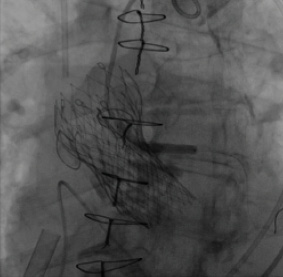

Figure 3. The “snorkel” technique provides left main coronary blood flow. A 3- X 30-mm Resolute drug-eluting stent (Medtronic) was positioned, extending from above the prosthetic valve leaflet insertion line into the left main coronary artery.

After successful release of the second CoreValve device at the level of the aortic annulus, the stent was repositioned and deployed in the native left main artery, with its proximal edge extending above the level of the initial CoreValve leaflet insertion line (Figure 3). This “snorkel” technique allowed blood flow into the left coronary system, enabling the patient to be weaned immediately from cardiopulmonary support.